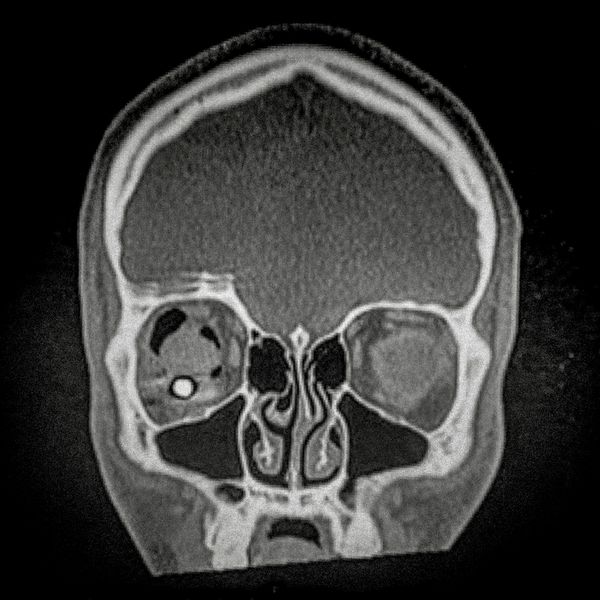

460 people have been seriously injured in their eyes, 34 of whom suffered total loss due to the indiscriminate use of pellets and tear gas bombs by the Carabineros de Chile special forces. The Carabineros fired their rubber bullets and tear gas guns directly into the faces of the protesters during the Chilean social outbreak between late 2019 and early 2020. This figure has made Chile the country with the world record for eye mutilation by state and security forces.

By early March 2020, around 3,838 people had been injured and according to the Chilean Society of Ophthalmologists and human rights organizations, 460 of them ended up with serious eye complications, loss of the eyeball, and also loss of sight. This figure has made Chile a world record for eye mutilation, due to the indiscriminate use of pellets and tear gas bombs by special forces of the Carabineros, who have shot their weapons directly into the faces of the protesters.